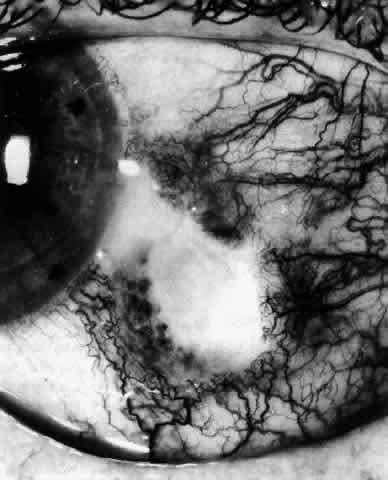

The sclera that is edematous is pushed forward, and the deep episcleral network is more congested than the superficial networks (Figs. 27 and 28). It is usually easy to ascertain by simple observation that the patient has scleritis and not episcleritis. However, it is not as easy to ascertain whether the patient has early necrotizing scleritis. It is in these patients that fluorescein angiography has considerable value, because the first changes are detectable in the ocular vasculature. Prompt and adequate treatment can prevent these changes from becoming irreversible.

Fig. 27. In scleritis, maximum congestion occurs in deep episcleral plexus, which is bowed forward by underlying scleral edema. Episcleral tissue is slightly infiltrated and superficial plexus is slightly congested (see Fig. 14). (Watson PG, Hayreh S, Awdry P: Episcleritis and scleritis. Br J Ophthalmol 52:278–279, 1968)

Fig. 28. Nodular scleritis. Both the anterior conjunctival slit and the deep scleral slit are displaced forward by the scleral edema. There is little separation between these two beams, indicating that all the edema is in the sclera and not in the overlying episclera. (Watson PG, Hayreh S, Awdry P: Episcleritis and scleritis. Br J Ophthalmol 52:278–279, 1968)